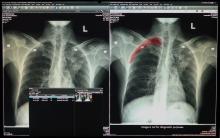

January 31, 2020 — One of the first imaging studies on the coronavirus (2019-nCoV) was published online today as radiologists scramble to find out how the virus presents in medical imaging. In just 30 days after the virus first appeared in China, it has spread to more than 8,200 confirmed cases and more than 170 deaths. Cases are now being reported in several countries, including the United States and Canada.